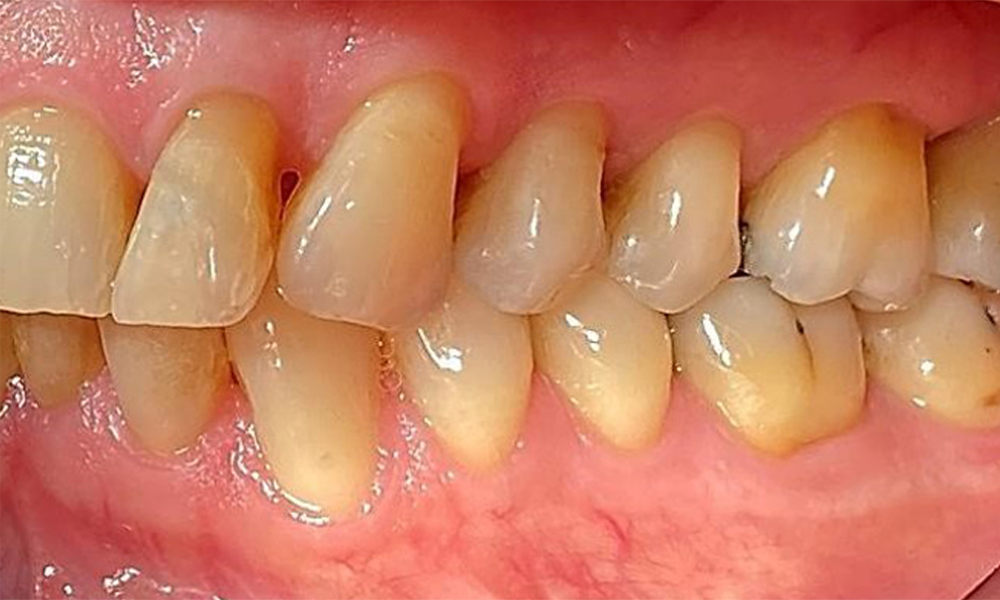

Pacientul prezintă dentiție completă cu 28 de dinți, care include obturații din amalgam și compozit pe molari și premolari. Există un spațiu marginal clinic vizibil la 14. Molarul 27 prezintă un inlay din aur adecvat. Se observă, de asemenea, atriții și abrazii generalizate. (Fig. 2, Fig. 3, Fig. 4, Fig. 5, Fig. 6)

Pacientul prezintă boală parodontală în stadiul II, gradul B (5). Profunzimile clinice de sondare observate, între 1 și 3 mm, se încadrează în limitele fiziologice. Localizat, s-au observat profunzimi de 5 mm, la nivel meziopalatin, atât pe 17, cât și pe 27. Se constată recesiuni generalizate de 1-3 mm, cu pierderi parțiale ale papilelor interdentare (Fig. 2, Fig. 3, Fig. 4)